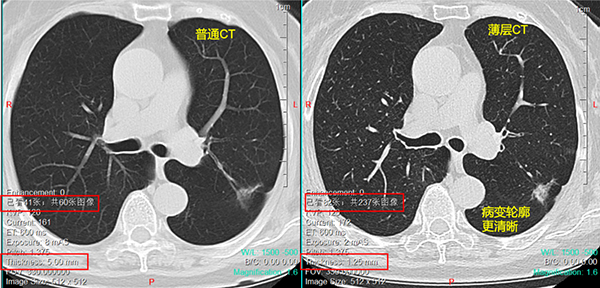

前面说过,CT是把人体水平分割成1.25~5mm的薄片,然后观察每一片上是否有病变。当每一层的厚度在2mm以下时,称为薄层CT,常见的薄层CT层厚就是1.25mm。

薄层CT是重建方式,而不是扫描方式,即一次CT扫描,即可以有5mm层厚的片子,也有1.25mm层厚的片子,患者不需要单独强调进行薄层CT扫描。薄层CT片子数量在200张以上,基于成本原因医院一般不会全部打印出来,只能在电脑上看,或是储存在光盘、U盘、云端。

薄层CT分辨率高,<5mm的结节也清晰可见,细节更明显,因此主要用于看磨玻璃结节和<1cm的实性结节。对于大病灶,薄层片子意义不大。一般看片子时,先在普通CT上找到主要病灶,再在薄层上看是否有多发结节,防止漏诊。